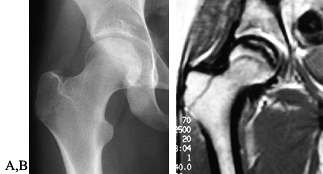

Figure 125.10. Images of a young patient with stage I, steroid-induced osteonecrosis of the right femoral head. A: The plain radiograph is within normal limits. B: The T1-weighted MRI shows a decreased signal intensity in the femoral head, characteristic of osteonecrosis.

|

Figure 125.11. Stage II osteonecrosis showing areas of sclerosis and radiolucency within the femoral head.

Figure 125.12. Stage III osteonecrosis. Note the crescent sign, indicating subchondral collapse without flattening of the articular surface.